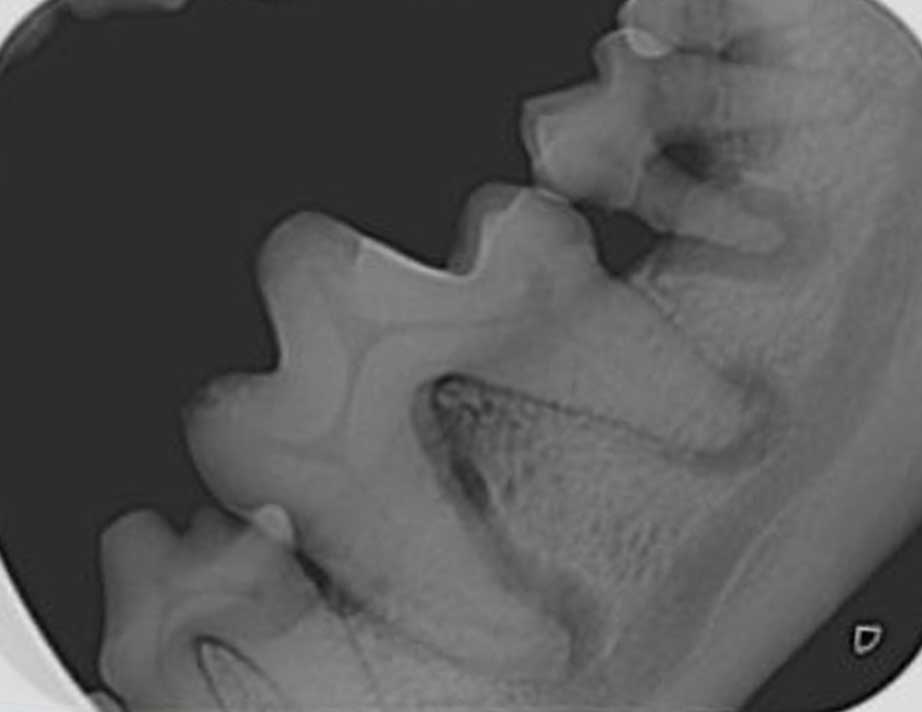

Figure 3. Dental radiograph of left mandibular first and second molar teeth in a mature dog with severe periodontal disease. Horizontal bone loss (overall loss of alveolar bone height) is present, as is vertical bone loss involving the mesial root of the first molar tooth and both roots of the second molar tooth. This explains the probing examination findings of increased probing depths in these regions, a stage three furcation exposure of the second molar tooth and a stage two furcation exposure of the first molar tooth. A periapical lesion of the distal root of the first molar tooth, which represents a perio-endo lesion, is an additional radiographic finding.